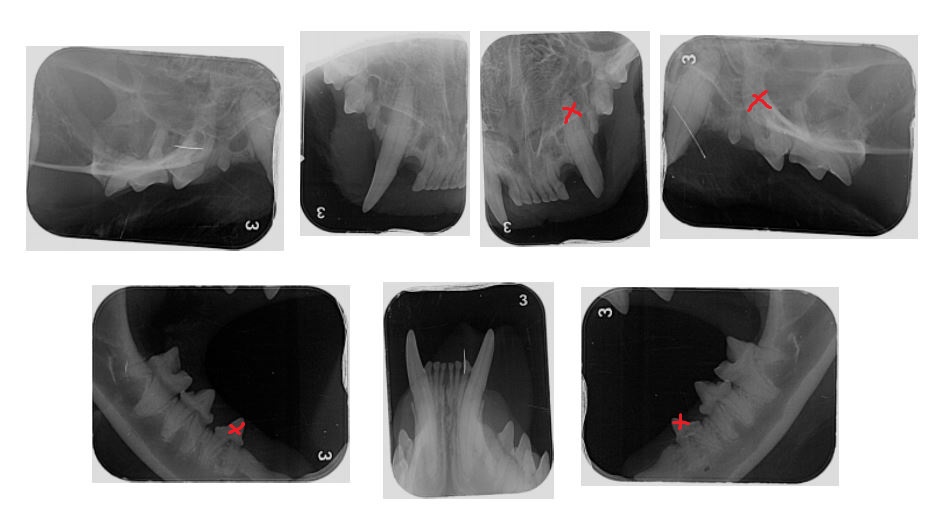

(Wo auf den Röntgenbildern sind eigentlich die kaputten Zähne? Als Laie seh ich da leider nix.)

Ich habe unten mal den Röntgen-Status von Tibby angehängt und die Zähnchen, die gezogen wurden, mit einem x markiert.

Das Problem ist auch wirklich nicht ganz so einfach zu erkennen. Wenn man ganz genau hinsieht, erkennt man, dass die Zahnwurzeln quasi "unsichtbar" werden, also verknöchern. Am besten kannst Du das erkennen, wenn Du die Zahnkronen mit dem Finger verdeckst und dir nur die Wurzeln ansiehst. Die erkennt man bei den betroffenen Zähnen kaum noch, weil sie genau so aussehen, wie der Kieferknochen drumherum und genau das ist das Problem bei FORL Typ 2. Die Wurzeln verknöchern.